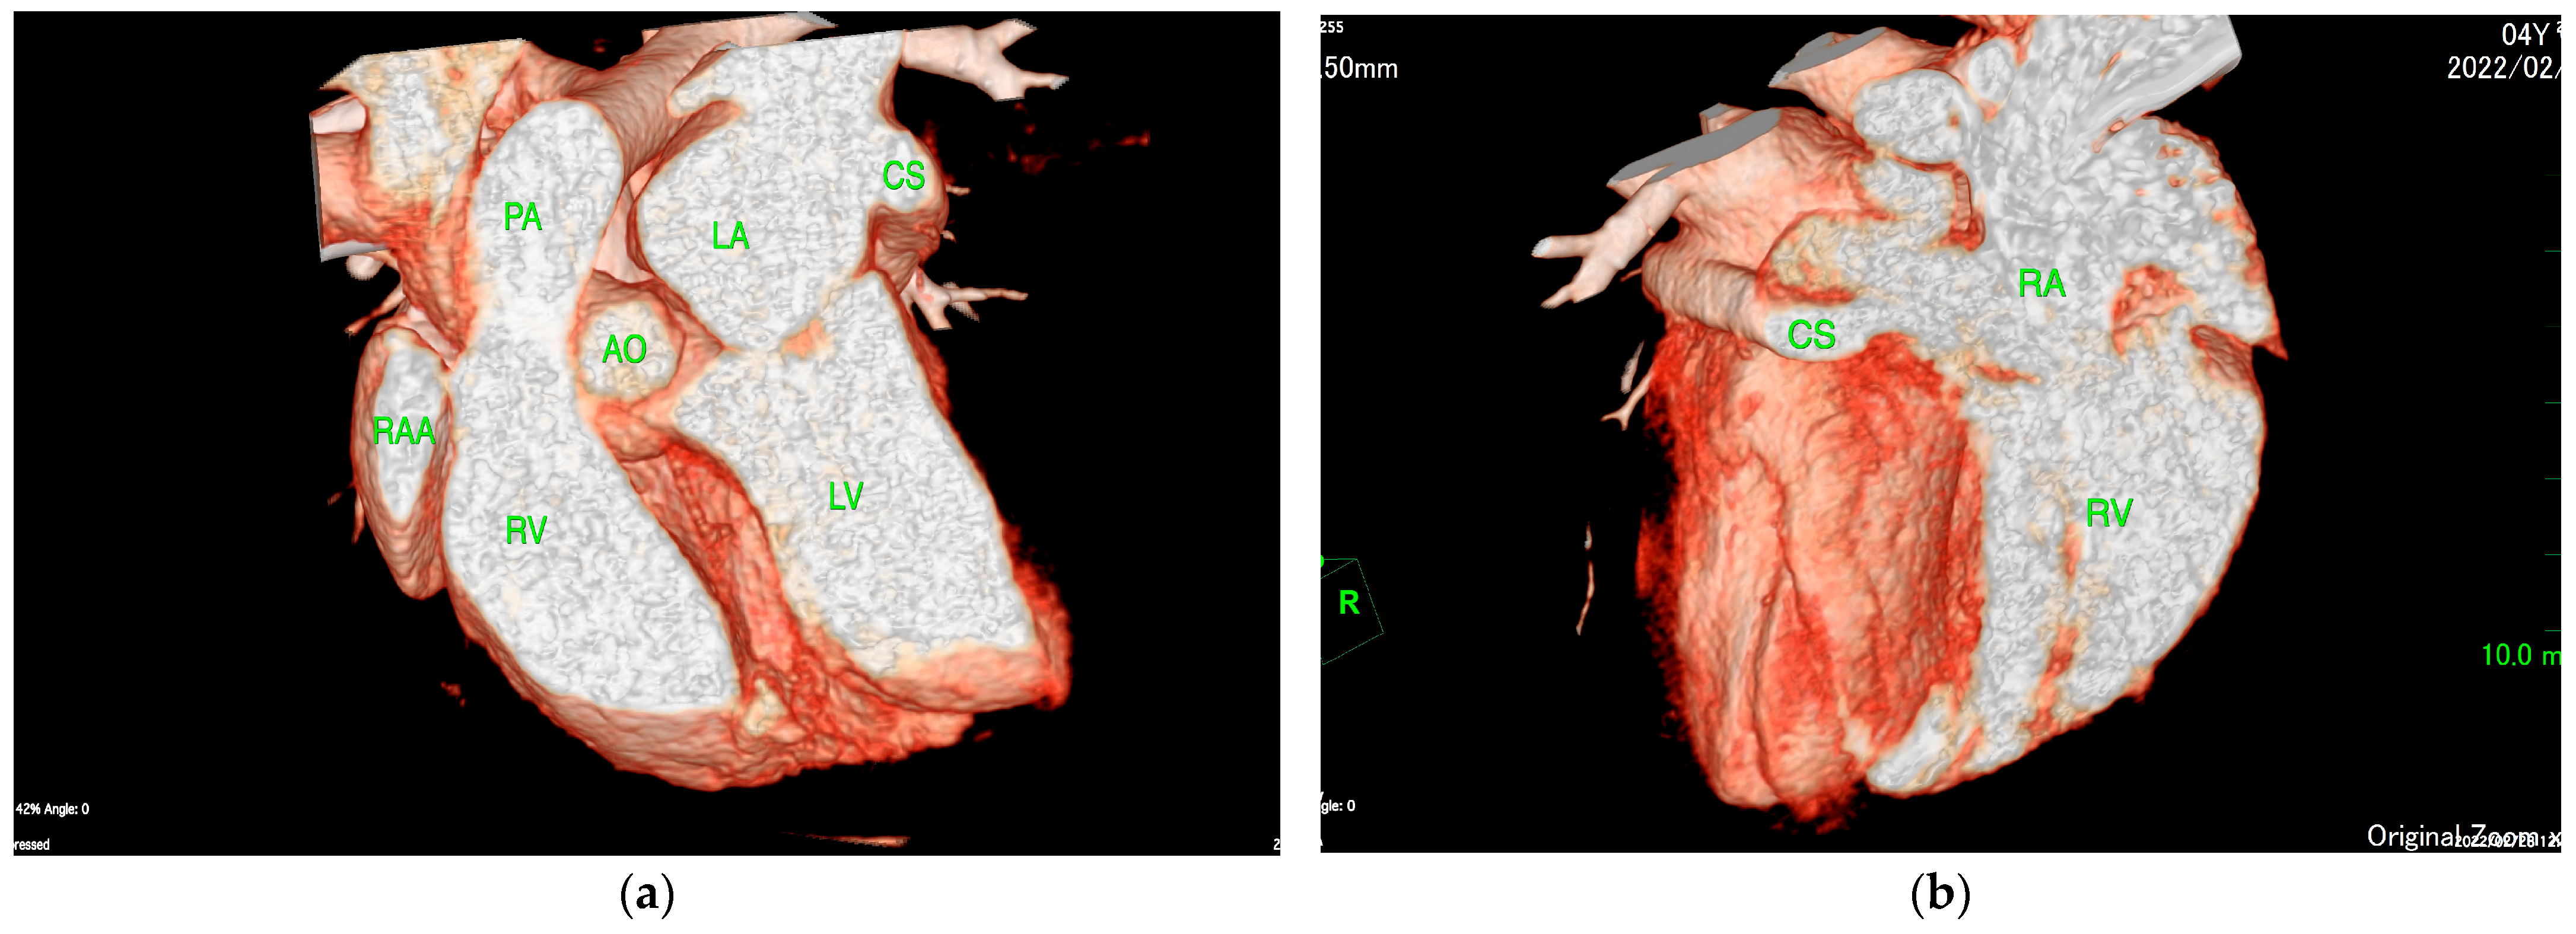

The ECG-gated CT showed communication between the LA and RA via the CS (Figure 2a). An enlargement of the CS, where the coronary artery measured 0.8 mm in diameter, whereas the CS measured 11.6 mm, was observed (Figure 2b). The CS drained normally into the RA; however, an ostium to the LA was seen, leading to the diagnosis of UCSS (Figure 3a). Under general anesthesia, TEE was also conducted using LISSENDO 880LE (Fujifilm Ltd., Tokyo, Japan) equipped with the 8–2 MHz phase array transesophageal probe (Fujifilm Ltd., Tokyo, Japan). With TEE, it was possible to identify the shunt as an abnormally large CS running along the cardiac wall (Figure 4).

When diagnosing UCSS, using just TTE may leave a risk of misdiagnosis [16]. In our case, the CS volume was overloaded. Considering that the mean diameter of the CS ostium in dogs is 5.5 ± 1.3 mm, the coronary sinus had become severely enlarged [17]. ECG-gated CT images showed that the diameter of the CS was 14.5 times larger than that of the coronary artery (Figure 2b). The largeness of the CS led to its appearance during the TTE as an irregular blood flow communicating between the LA to the RA, thus supporting the initial misdiagnosis of ASD. It is important to consider the possibility of extracardiac blood flow when no intracardiac defect is identifiable.

Figure 2. (a) ECG-gated CT multiplanar reconstruction (left oblique sagittal view) demonstrating the irregular communication between the RA and LA (arrow) that is formed by the unroofed CS. The opening in the CS allows blood flow from the RA to the LA. (b) ECG-gated CT volume rendering (sagittal slice, left lateral view, observed from the right) showing the markedly enlarged CS (red arrow) compared to the CA (yellow arrow). The CS measures 11.6 mm in diameter and is abnormally large compared to the CA, measuring 0.8 mm. CS, coronary sinus; CA, coronary artery LA, left atrium; LV, left ventricle; RA, right atrium; RV, right ventricle; SVC, superior vena cava.

Figure 3. (a) ECG-gated CT volume rendering (sagittal slice, right lateral view, observed from the left) showing the CS connecting to the LA. (b) ECG-gated CT volume rendering (oblique sagittal slice, right lateral view, observed from the right) showing the CS connecting to the RA. CS, coronary sinus; RA, right artery; RV, right ventricle; LA, left atrium; LV, left ventricle; AO, aorta; PA, pulmonary artery; RAA, right atrial appendage.